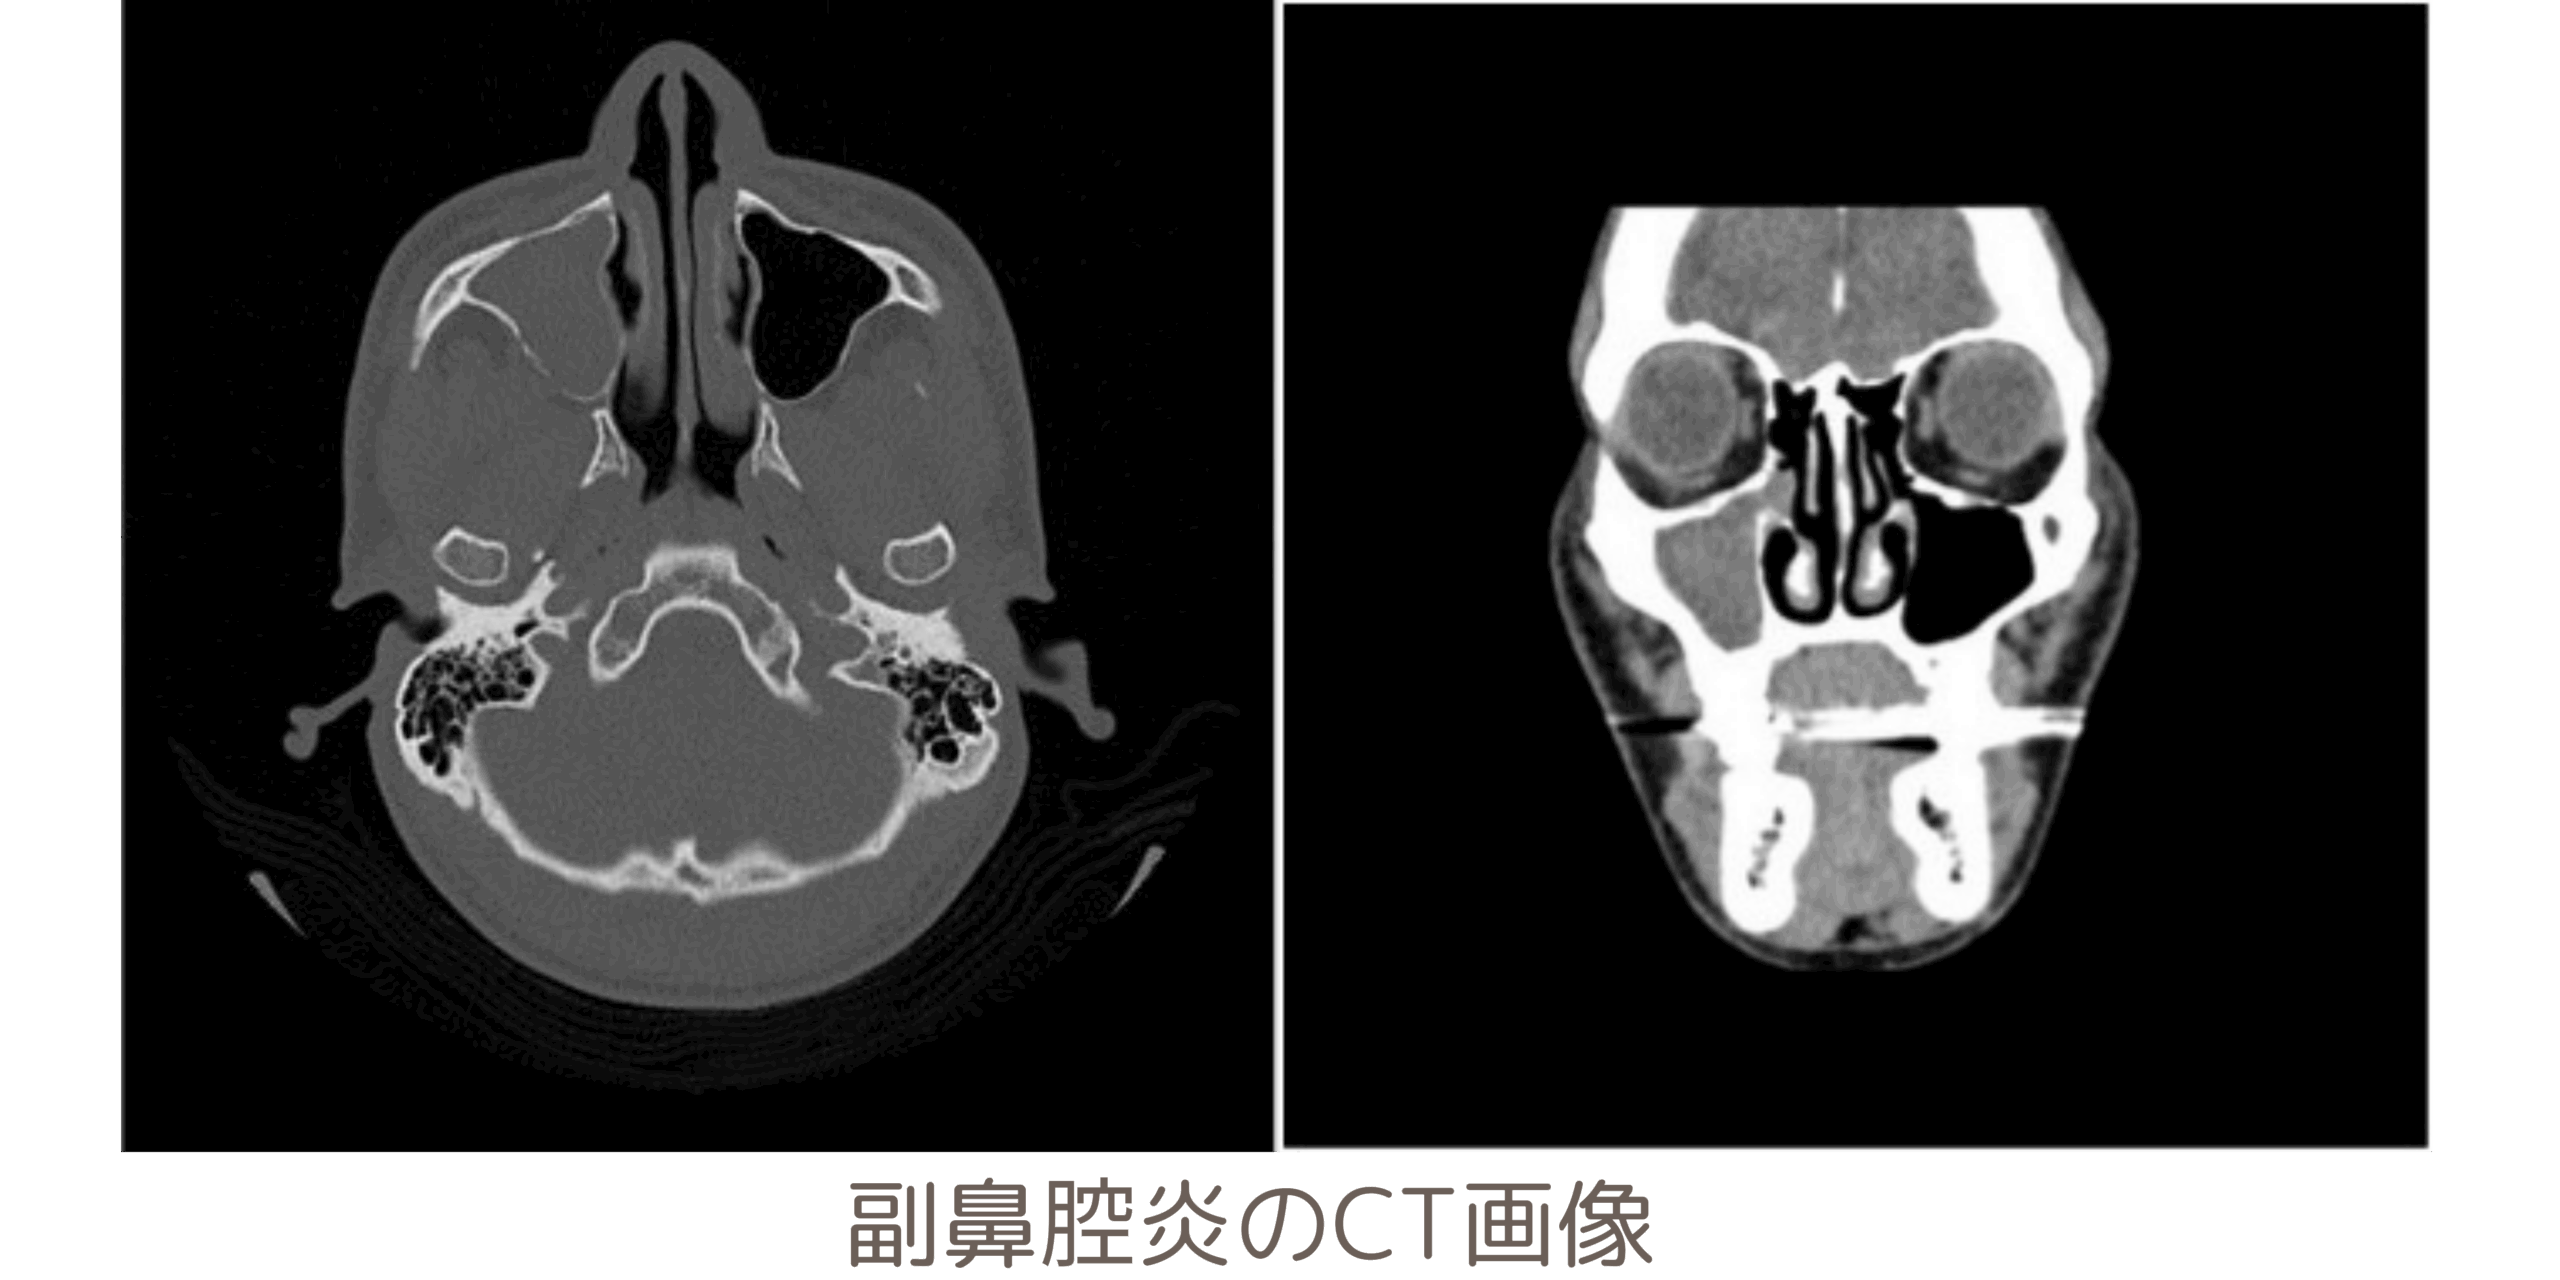

頭部のCT検査では、脳出⾎やくも膜下出⾎などの出⾎を伴う病気や⾻折、副⿐腔炎なども確認できます。